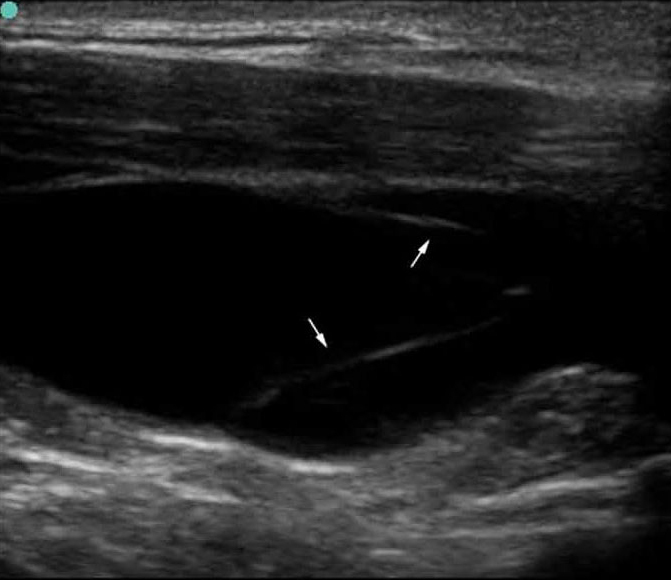

S Series: IJV Long Axis Valve Open.